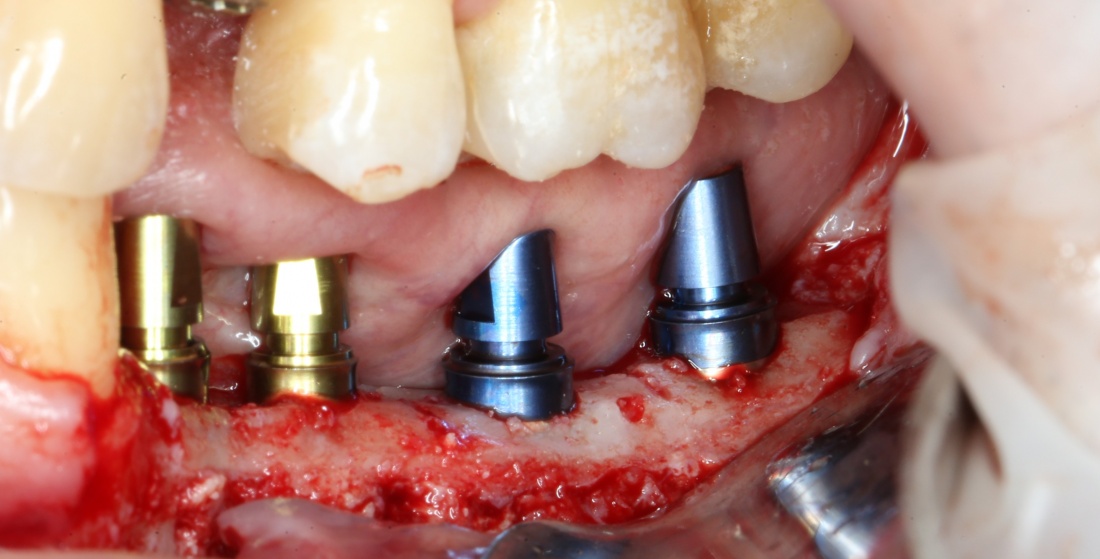

Я зафиксировал костный блок практически без адаптации на несколько винтов. Обрати внимание, что винты находятся в зоне, где не планируется установка имплантатов. Фиксация должна быть надежной, поскольку мне еще предстояла подготовка лунок для имплантатов. Трех винтов для этого вполне достаточно.

Дальнейшая адаптация костного блока свелась к сглаживанию острых краев. После чего я приступил к подготовке лунок и установке имплантатов.

Установка имплантатов.

Напомню, что для этой работы я выбрал субкрестальные имплантаты Ankylos C/X. Они прекрасно сочетаются с любым методом остеопластики.

Я не планирую установку супраструктур или коронок, поэтому на уровень первичной стабильности можно положить болт. Даже наоборот — чем меньше крутящий момент при установке, тем лучше. Для имплантатов Ankylos и подобных им, это особенно важно. В общем, момент силы при установке — не более 10-15 Нсм.

Ремарка: имплантаты с предустановленными имплантодержателями хороши тем, что с ними легко контролировать позиционирование имплантатов. В случае с Ankylos С/Х - еще и крутящий момент. Имплантодержатель должен отсоединяться от имплантата с легким щелчком. Если его клинит, и тебе приходится прикладывать для этого усилия, то ты, однозначно, превысил момент силы во время установки имплантата. Следовательно, жди проблем.

Глянем на то, что получилось:

Осталось адаптировать костный блок (убрать острые края), проверить его фиксацию и, при необходимости, добавить винты. Десятисекундное дело.